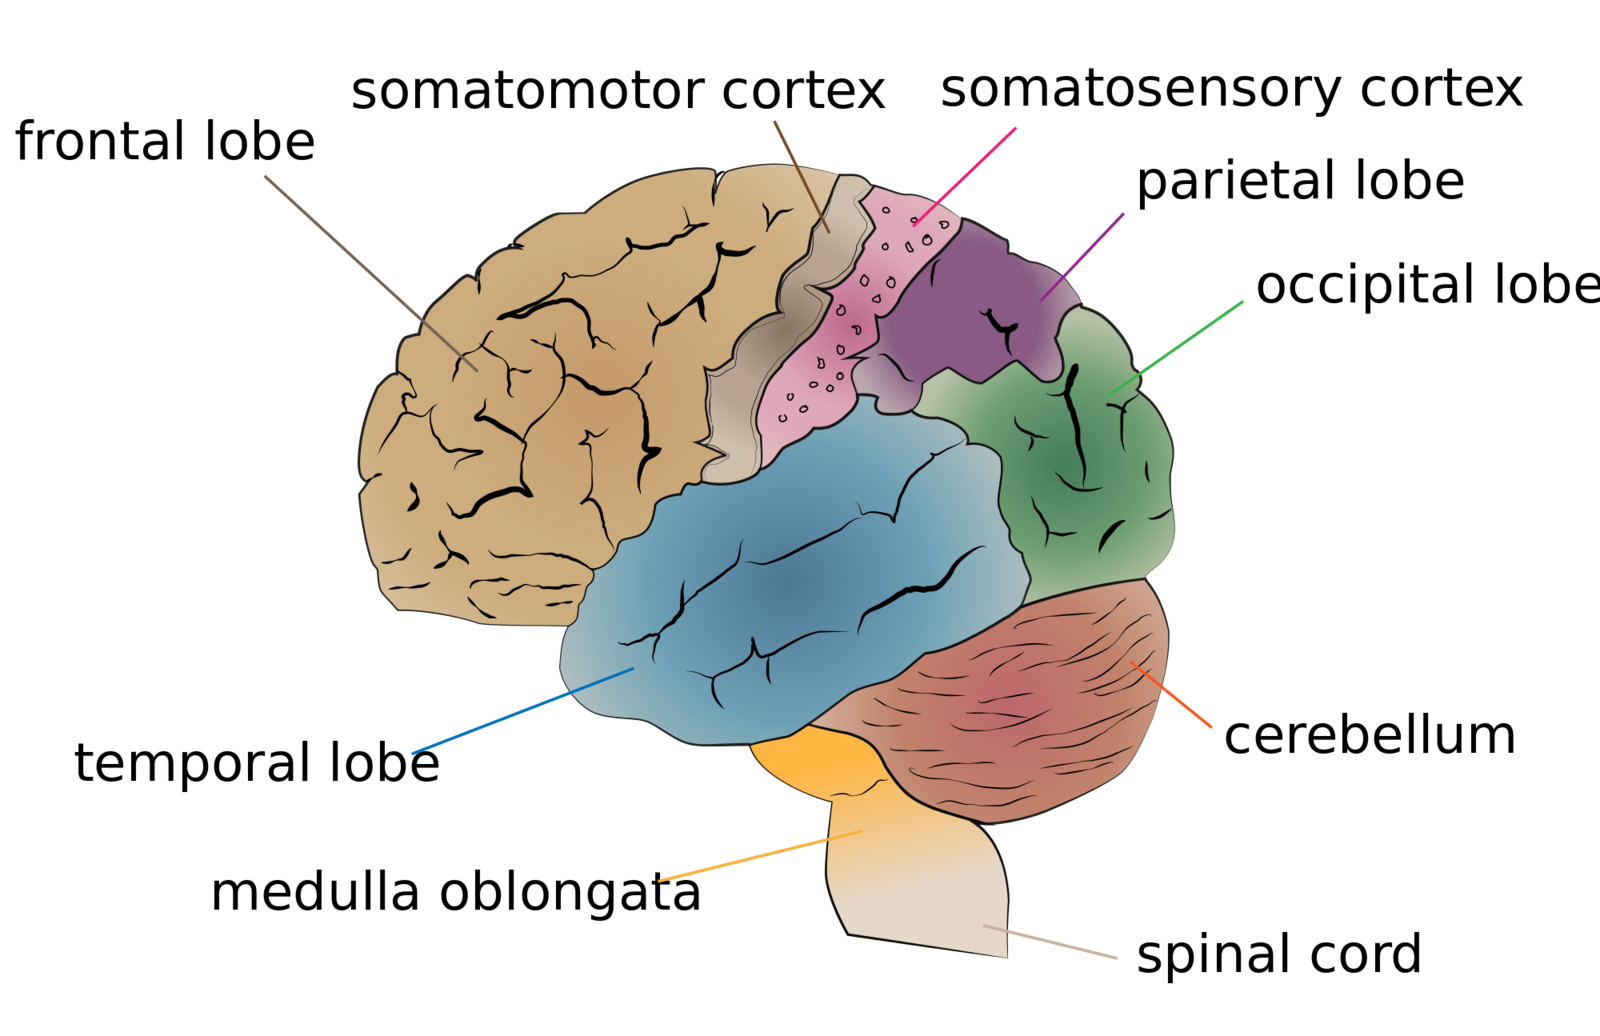

Creative Commons – Simple Pictures, Images, Video Clips, and/or Gifs that help illustrate the following:

- Brain Surface Anatomy – Lobes and Cerebellum

-

Frontal Lobe, Parietal Lobe, Temporal Lobe, and Occipital Lobe -

Parts of the Human Brain

Basic structures of the brain highlighted. - Brain Surface Anatomy – Primary Motor Cortex, Primary Somatosensory Cortex

Figure 16.21. The human cerebral cortex includes the frontal, parietal, temporal, and occipital lobes.

Cerebrum lobes. - Brain Deep Anatomy – Hypothalamus, Thalamus, Midbrain, Medulla Oblongata, Pons